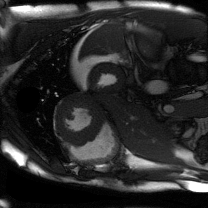

Supervised Deep-Learning (DL)-based reconstruction algorithms have shown state-of-the-art results for highly-undersampled dynamic Magnetic Resonance Imaging (MRI) reconstruction. However, the requirement of excessive high-quality ground-truth data hinders their applications due to the generalization problem. Recently, Implicit Neural Representation (INR) has appeared as a powerful DL-based tool for solving the inverse problem by characterizing the attributes of a signal as a continuous function of corresponding coordinates in an unsupervised manner. In this work, we proposed an INR-based method to improve dynamic MRI reconstruction from highly undersampled k-space data, which only takes spatiotemporal coordinates as inputs. Specifically, the proposed INR represents the dynamic MRI images as an implicit function and encodes them into neural networks. The weights of the network are learned from sparsely-acquired (k, t)-space data itself only, without external training datasets or prior images. Benefiting from the strong implicit continuity regularization of INR together with explicit regularization for low-rankness and sparsity, our proposed method outperforms the compared scan-specific methods at various acceleration factors. E.g., experiments on retrospective cardiac cine datasets show an improvement of 5.5 ~ 7.1 dB in PSNR for extremely high accelerations (up to 41.6-fold). The high-quality and inner continuity of the images provided by INR has great potential to further improve the spatiotemporal resolution of dynamic MRI, without the need of any training data.